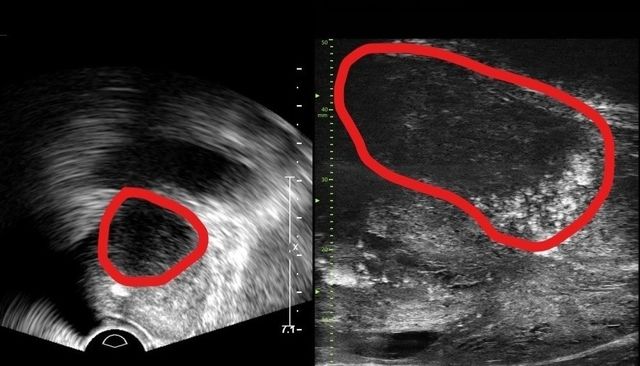

분당서울대학교병원 비뇨의학과는 기존 초음파보다 3배 더 높은 해상도의 실시간 영상을 통해 전립선 종양 평가가 가능한 마이크로 초음파 장비를 국내 최초로 도입했다고 밝혔다.

29MHz 마이크로 초음파를 사용하는 이 장비는 전립선과 주변의 해부학적 구조를 선명히 표시하고 표적 조직검사를 유도한다. 의심 영역을 실시간으로 확인하면서 전립선 조직의 미세한 변화와 병변을 식별하고 조직검사 채취를 위한 바늘을 정확한 위치에 삽입할 수 있다는 장점이 있다.

또한, 전립선 암 진단을 위한 초음파 검사 가이드인 PRI-MUS(Prostate Risk Identification Using Micro-Ultrasound) 위험도 식별 시스템과 연계돼있어 전립선암 병변의 악성 가능성 평가는 물론, 어느 부분에서 조직을 채취해야 하는지 정확히 판단할 수 있게 한다. PRI-MUS는 초음파 상 병변의 모양이나 크기를 자동으로 판단해 병변의 악성도를 1~5단계(높을수록 위험)로 분류하기 때문에 불필요한 조직검사를 줄이면서도 암을 놓치지 않게 돕는다.

기존의 경직장 초음파는 해상도가 낮아 전립선 종양, 특히 작은 암 병변을 감지하는 데 한계가 있었다. 하지만 마이크로 초음파의 높은 해상도와 실시간 영상의 시각화는 자기공명영상(MRI)으로 발견할 수 없는 전립선암을 찾을 때도 충분히 기여할 것으로 기대하고 있다. MRI 검사 보다 환자의 신체적, 심리적, 경제적 부담도 적을 수밖에 없다.